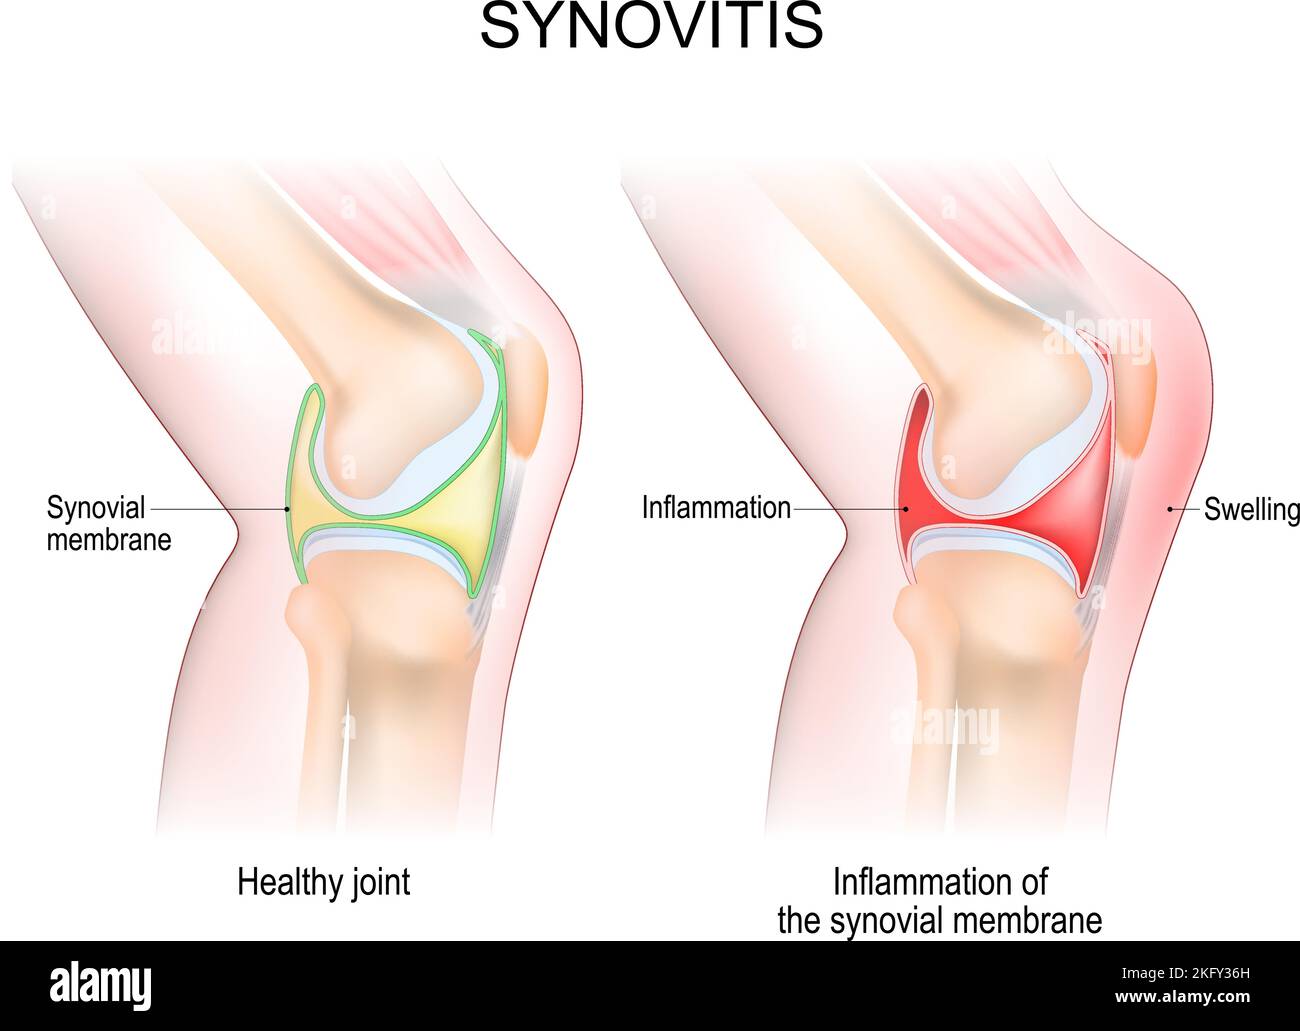

synovitis of a Knee. Close-up of normal joint, and knee with inflammation of the synovial membrane. Signs and symptoms of the disease. side view Stock Vectorhttps://www.alamy.com/image-license-details/?v=1https://www.alamy.com/synovitis-of-a-knee-close-up-of-normal-joint-and-knee-with-inflammation-of-the-synovial-membrane-signs-and-symptoms-of-the-disease-side-view-image491705385.html

synovitis of a Knee. Close-up of normal joint, and knee with inflammation of the synovial membrane. Signs and symptoms of the disease. side view Stock Vectorhttps://www.alamy.com/image-license-details/?v=1https://www.alamy.com/synovitis-of-a-knee-close-up-of-normal-joint-and-knee-with-inflammation-of-the-synovial-membrane-signs-and-symptoms-of-the-disease-side-view-image491705385.htmlRF2KFY36H–synovitis of a Knee. Close-up of normal joint, and knee with inflammation of the synovial membrane. Signs and symptoms of the disease. side view

synovitis. Close-up. comparison and difference between a healthy joint and a joint with inflammation of the synovial membrane. Signs and symptoms Stock Vectorhttps://www.alamy.com/image-license-details/?v=1https://www.alamy.com/synovitis-close-up-comparison-and-difference-between-a-healthy-joint-and-a-joint-with-inflammation-of-the-synovial-membrane-signs-and-symptoms-image425406050.html

synovitis. Close-up. comparison and difference between a healthy joint and a joint with inflammation of the synovial membrane. Signs and symptoms Stock Vectorhttps://www.alamy.com/image-license-details/?v=1https://www.alamy.com/synovitis-close-up-comparison-and-difference-between-a-healthy-joint-and-a-joint-with-inflammation-of-the-synovial-membrane-signs-and-symptoms-image425406050.htmlRF2FM2WN6–synovitis. Close-up. comparison and difference between a healthy joint and a joint with inflammation of the synovial membrane. Signs and symptoms